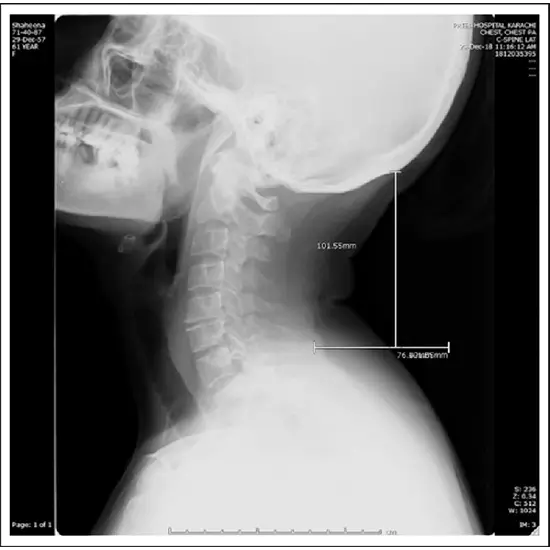

An X-Ray Cervical Spine Lateral View is an imaging test that aids in the detection of cervical spine fractures, dislocations, bone lesions, and degenerative disorders. It helps visualize any neck and cervical spine abnormalities.

• To diagnose long-lasting neck or upper back discomfort.

• To check for spinal fractures (vertebrae).

• To diagnose spine tumors, arthritis, osteoporosis, or infections

• To diagnose disc abnormalities such as spondylolisthesis, degeneration, or ruptured disc.

• To examine for anomalies in the spine's curvature, such as lordosis, kyphosis, scoliosis, or birth deformities.